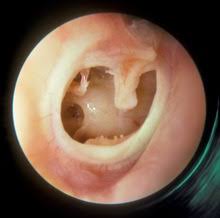

The principal causative organisms are pseudomonas aeruginosa, proteus sp, staphylococcus, other gram negative and anaerobic bacteria. It is predominantly a disease of the developing world. 1) perforation of the tympanic membrane due to acute infection or tympanotomy tube, 2) discharge from the middle ear (otorrhea), and 3) prolonged duration (;gt;2 wk). Chronic suppurative otitis media presents with persistent or recurrent otorrhea through a perforated tympanic membrane (active), or with a dry but permanent perforation of the tympanic membrane. The condition is often seen in patients with a history of acute otitis media with tm rupture and presents with painless otorrhea and conductive hearing loss. Chronic suppurative otitis media 1. Clinical features are recurrent otorrhoea through a tympanic perforation, with conductive hearing loss of varying severity. Chronic suppurative otitis media (csom) is the result of an initial episode of acute otitis media and is characterized by a persistent discharge from the middle ear through a tympanic perforation.

Chronic suppurative otitis media (csom) is defined as 'a chronic inflammation of the middle ear and mastoid cavity, which presents with recurrent ear discharges (otorrhoea) through a tympanic perforation'.

Chronic suppurative otitis media is a serious disease with a bacterial infection in the middle ear. It is predominantly a disease of the developing world. Chronic suppurative otitis media (csom) involves a cycle of inflammation, ulceration, granulation and infection in the middle ear. Chronic suppurative otitis media (csom) is a chronic inflammation of the middle ear and mastoid cavity that is characterised by discharge from the middle ear through a perforated tympanic membrane for at least 6 weeks. Patients with chronic suppurative otitis media (csom) respond more frequently to topical therapy than to systemic therapy. Chronic suppurative otitis media presents with persistent or recurrent otorrhea through a perforated tympanic membrane (active), or with a dry but permanent perforation of the tympanic membrane. Chronic suppurative otitis media (csom) is a chronic inflammation of the middle ear and mastoid cavity. Acute otitis media and blockage of a eustachian tube are among the causes of chronic suppurative otitis media. Chronic suppurative otitis media (csom): Like csom, ome often occurs after acute otitis media (aom) … 1, 2, 3 chronic suppuration can occur. Chronic suppurative otitis media 1. Chronic suppurative otitis media (csom) is defined as 'a chronic inflammation of the middle ear and mastoid cavity, which presents with recurrent ear discharges (otorrhoea) through a tympanic perforation'.